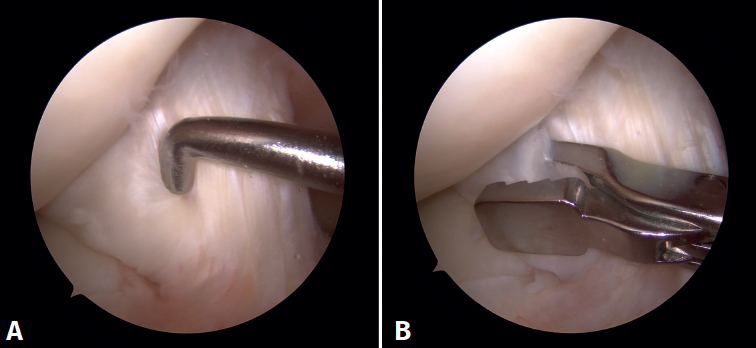

reaca.32385.fs2409018-figura2.png

Figura 2. Imagen de resonancia magnética del quiste sinovial localizado en el ligamento cruzado anterior en cortes sagitales. A: secuencia DP FS en corte sagital de la rodilla; B: secuencia DP T1 en corte sagital de la rodilla.

En las pruebas complementarias no presentaba alteraciones óseas en las radiografías en carga anteroposterior y lateral de rodilla. El estudio mediante RM evidenció un ganglión sinovial intercondilar de 25 mm (Figura 2).